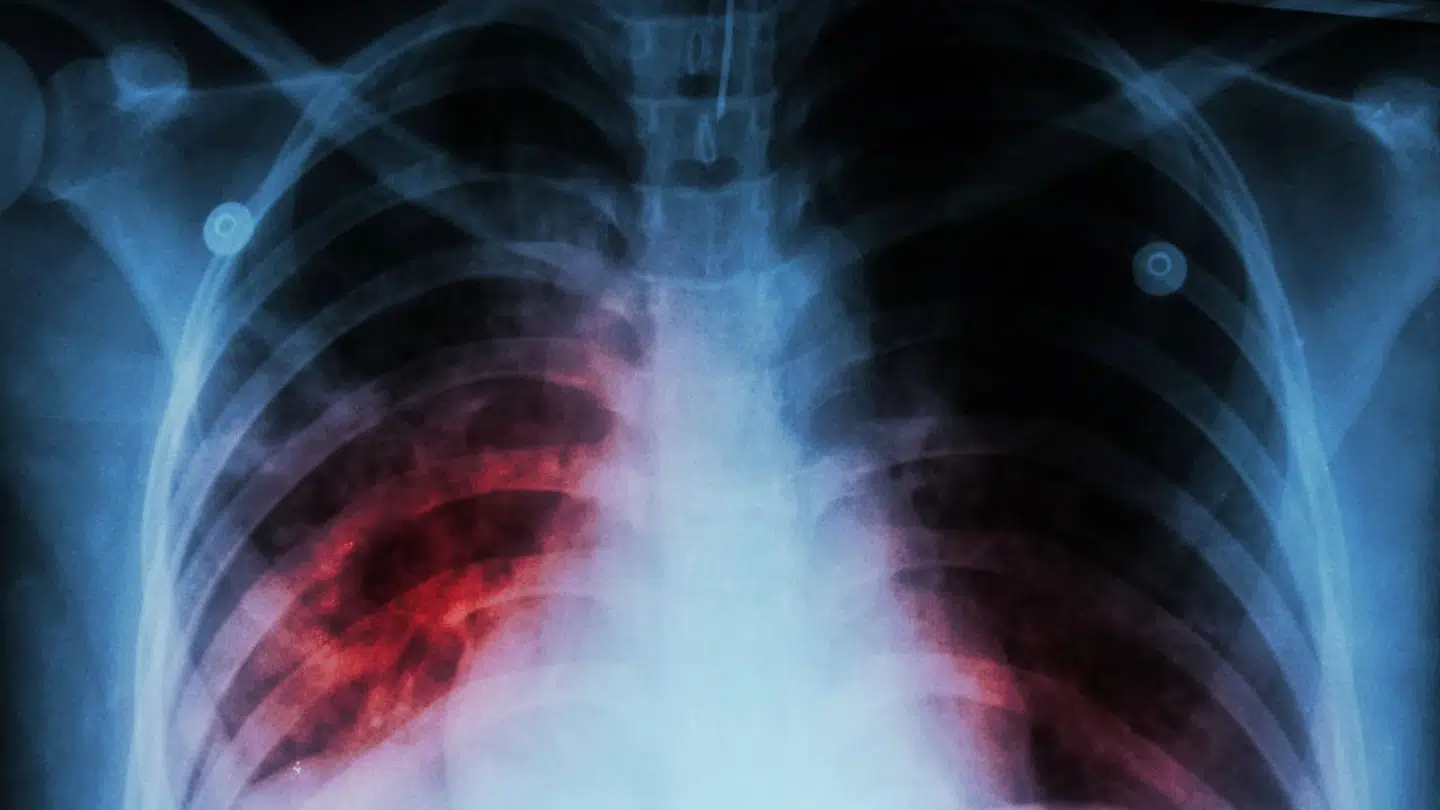

Statens Serum Institut melder om fire nye tilfælde af multi-resistent tuberkulose i Danmark alene i år. Det er, hvad vi normalt ser på to år, siger eksperterne.

De seneste mange år har der årligt været cirka to tilfælde af den frygtede lungesygdom herhjemme. Nu bemærker eksperterne fra Statens Serum Institut imidlertid, at der i løbet af årets fem første måneder allerede har været fire tilfælde.

Udviklingen bekymrer forskerne. Det er nemlig ikke bare en alvorlig sygdom, som er dyr og besværlig at behandle. Sygdommen er også forbundet med mange komplikationer og bivirkninger for den enkelte patient.

Sygdommen multi-resistent tuberkulose er en af de største trusler på verdensplan. I Danmark bliver langt de fleste helbredt, men i resten af verden kan man kun helbrede omkring halvdelen af de cirka 500.000 multi-resistente patienter.

Der går cirka halvandet år fra en person får stillet diagnosen, til patienten er rask, og hver behandling koster cirka en million kroner.